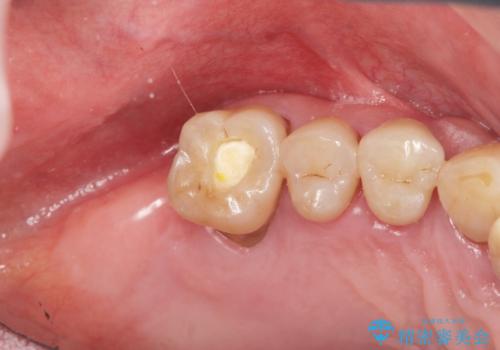

- 「歯がぐらぐらして噛めない、歯を抜いて欲しい、またしっかりと噛めるようになりたい。」、と歯周病治療を希望され来院されました。

歯の根本まで骨吸収が進み、ぐらぐらになってしまった歯を抜去し骨の造成を行ったのちインプラント治療を計画します。